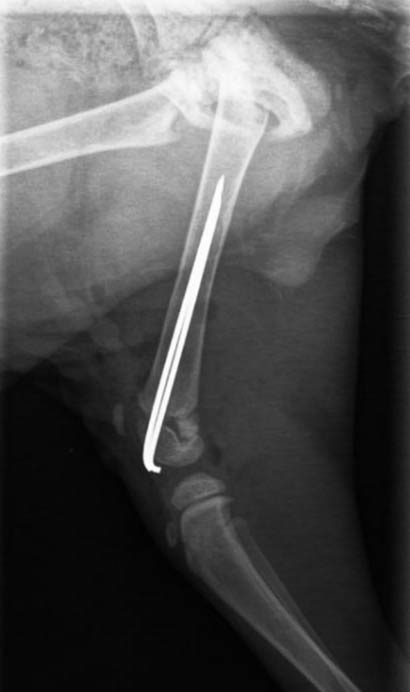

Das kleine Fellbündle wurde gefunden und ins Tierheim gebracht (und leider nicht wieder abgeholt), dort stellte man fest, dass er schreckliche Schmerzen im hinteren Bereich hatte. Um dem hübschen Bub Erleichterung verschaffen zu können, wurde er gleich dem Tierarzt vorgestellt. Leider gab es dort keine guten Neuigkeiten, er hatte sich einen schweren Bruch des Oberschenkels zugezogen, welcher sofort operiert werden musste.